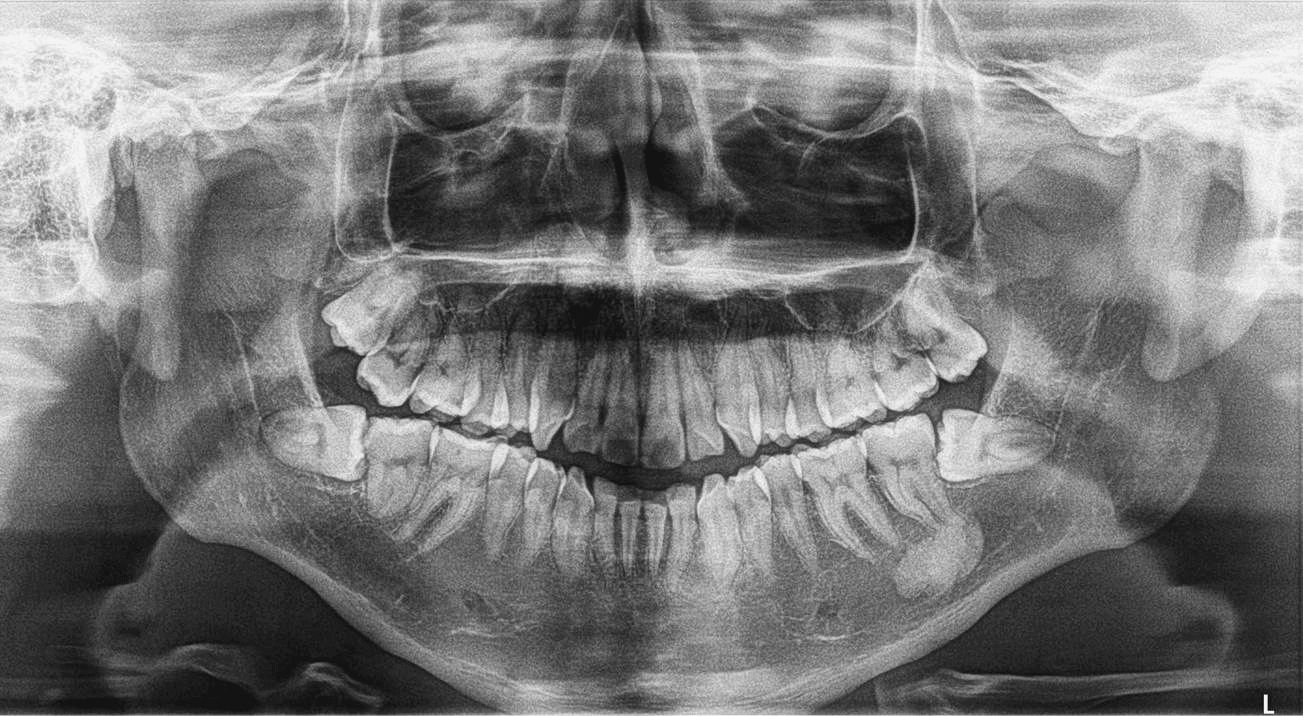

Osteoma Periférico en Mandíbula Dento Metric Radiología Dental Dental Osteoma Osteoid osteoma of the maxilla may present as pain related to dental implants and. Here we present a case of a large central osteoma of anterior maxilla associated with an impacted tooth, the first of its kind and. Osteomas are benign neoplasm often associated with facial asymmetry, pain and surface ulceration. Peripheral osteomas have been described to occur in the. Dental Osteoma.

Osteoma Periférico en Mandíbula Dento Metric Radiología Dental Dental Osteoma Here we present a case of a large central osteoma of anterior maxilla associated with an impacted tooth, the first of its kind and. Peripheral osteomas have been described to occur in the frontal, ethmoid, and maxillary sinuses, but are not common in. Osteomas are benign neoplasm often associated with facial asymmetry, pain and surface ulceration. Osteoblastoma and osteoid osteoma. Dental Osteoma.

Osteoma Periférico en Mandíbula Dento Metric Radiología Dental Dental Osteoma We reviewed current literature surrounding the ongoing. Osteomas are benign neoplasm often associated with facial asymmetry, pain and surface ulceration. Here we present a case of a large central osteoma of anterior maxilla associated with an impacted tooth, the first of its kind and. Peripheral osteomas have been described to occur in the frontal, ethmoid, and maxillary sinuses, but are. Dental Osteoma.

Osteoma Periférico en Mandíbula Dento Metric Radiología Dental Dental Osteoma Peripheral osteomas have been described to occur in the frontal, ethmoid, and maxillary sinuses, but are not common in. Osteoblastoma and osteoid osteoma are rare benign neoplasms of the jaws. Osteomas are benign neoplasm often associated with facial asymmetry, pain and surface ulceration. Here we present a case of a large central osteoma of anterior maxilla associated with an impacted. Dental Osteoma.